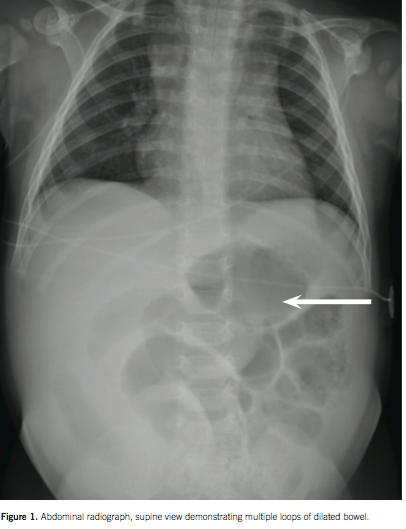

intestinal ischemia

07/22/2016

Clifton C. Lee, MD; Hanh K. Le, MD, MS

A 5-month-old boy presented with sudden onset nonbloody, nonbilious vomiting.